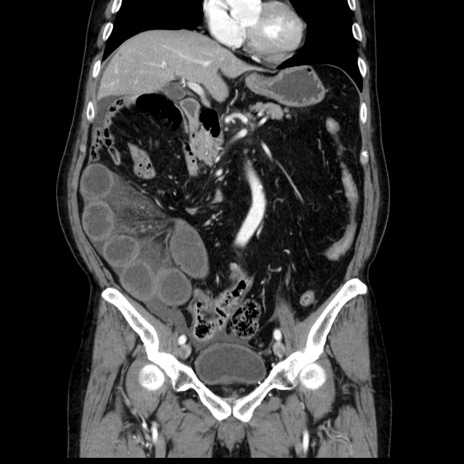

症例30(冠状断像)

【症例】80歳代男性

【主訴】臍周囲痛

【現病歴】約6時間前から臍下部痛が出現。次第に腹部膨隆・背部痛も生じてきたため来院。背部痛の場所は変化しない。

【身体所見】意識清明、BT 36.3℃、BP  131/87mmHg、P 87bpm、SpO2 100%(RA)、臍周囲自発痛・圧痛あり、反跳痛なし、自発痛部位に一致して板状硬あり、腹部膨隆、腸雑音減弱、CVA tenderness両側陰性。

【データ】WBC 19600、CRP 0.33